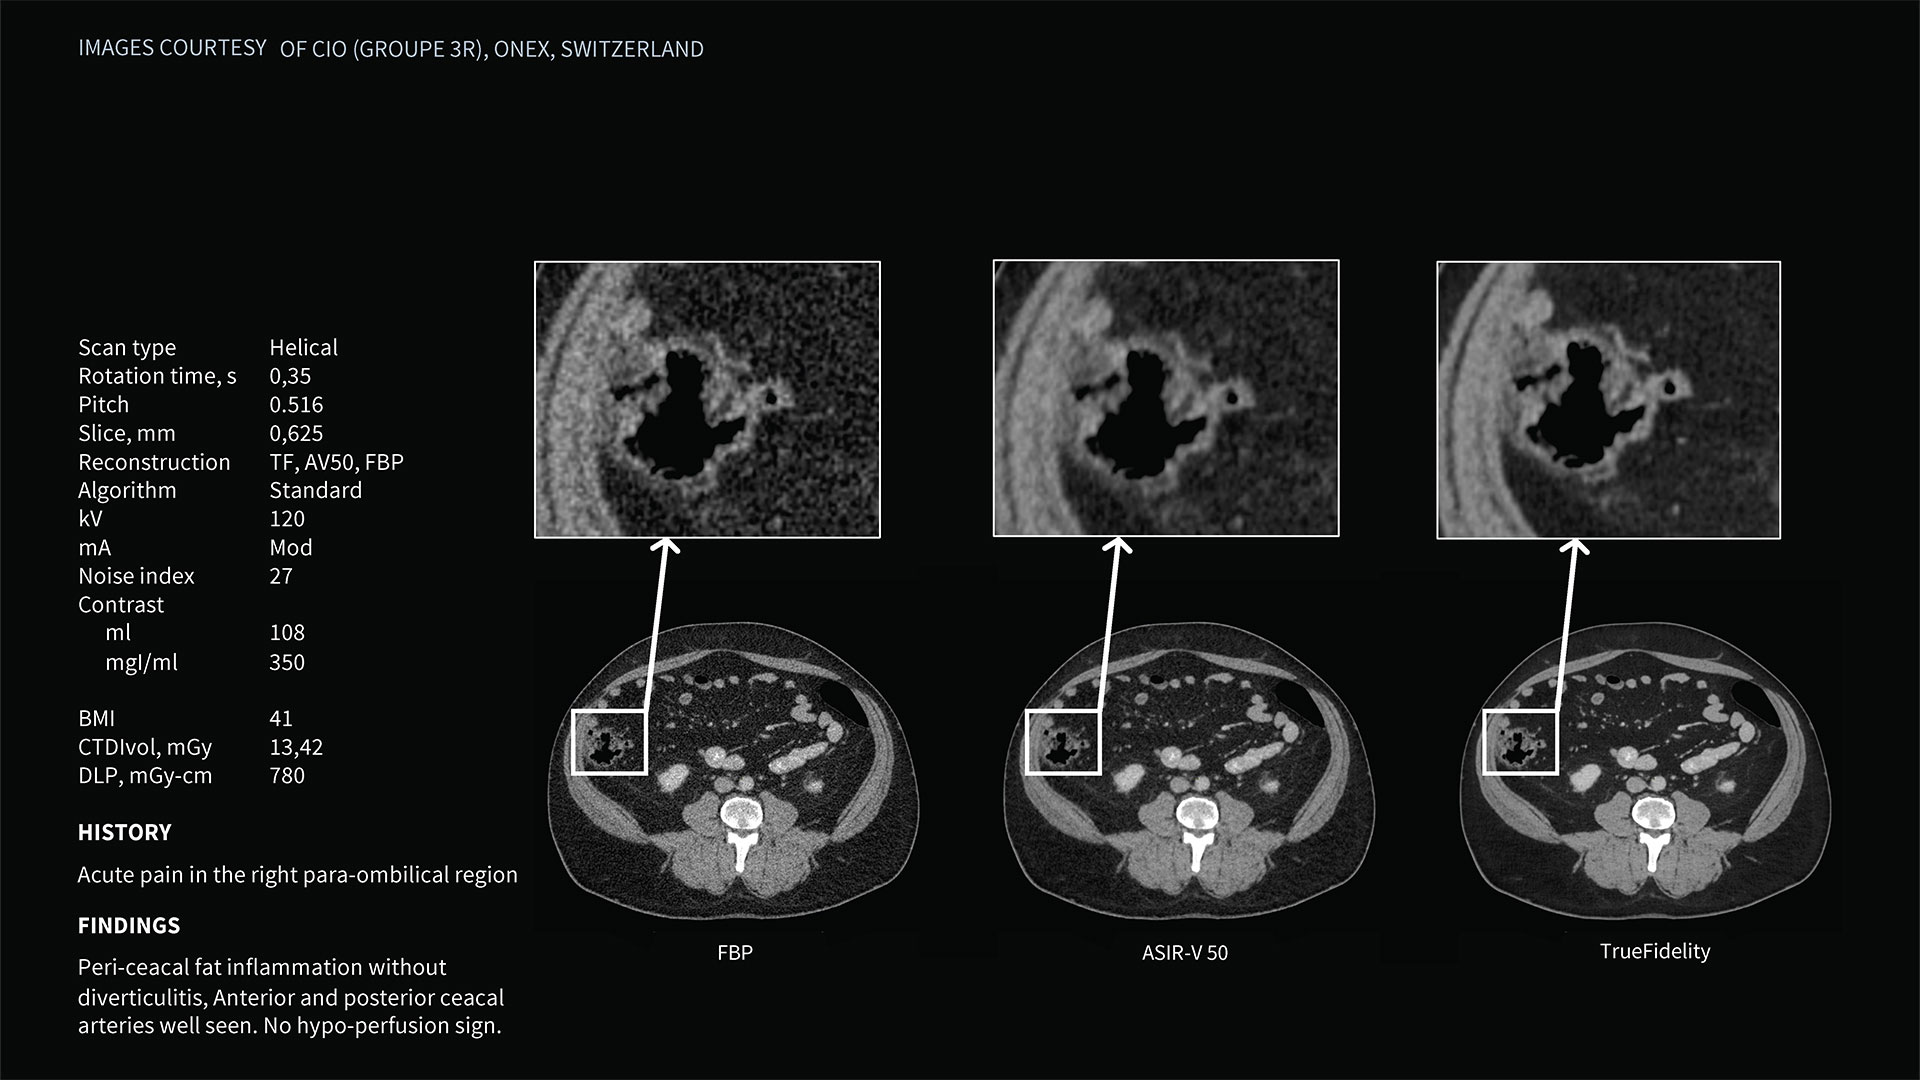

Deep learning image reconstruction, higher special resolution at 0.23 mm

Address individual clinical needs, moving seamlessly from one scan mode to the next. Image with a stunning 0.23 mm spatial resolution, then switch to rapid kV switching for full 50 cm FOV spectral imaging of the entire body. Choose up to six times reduction in motion artifact using SnapShot Freeze 2¹ for coronary artery CTA and reduce all-round dose with next-generation iterative reconstruction.